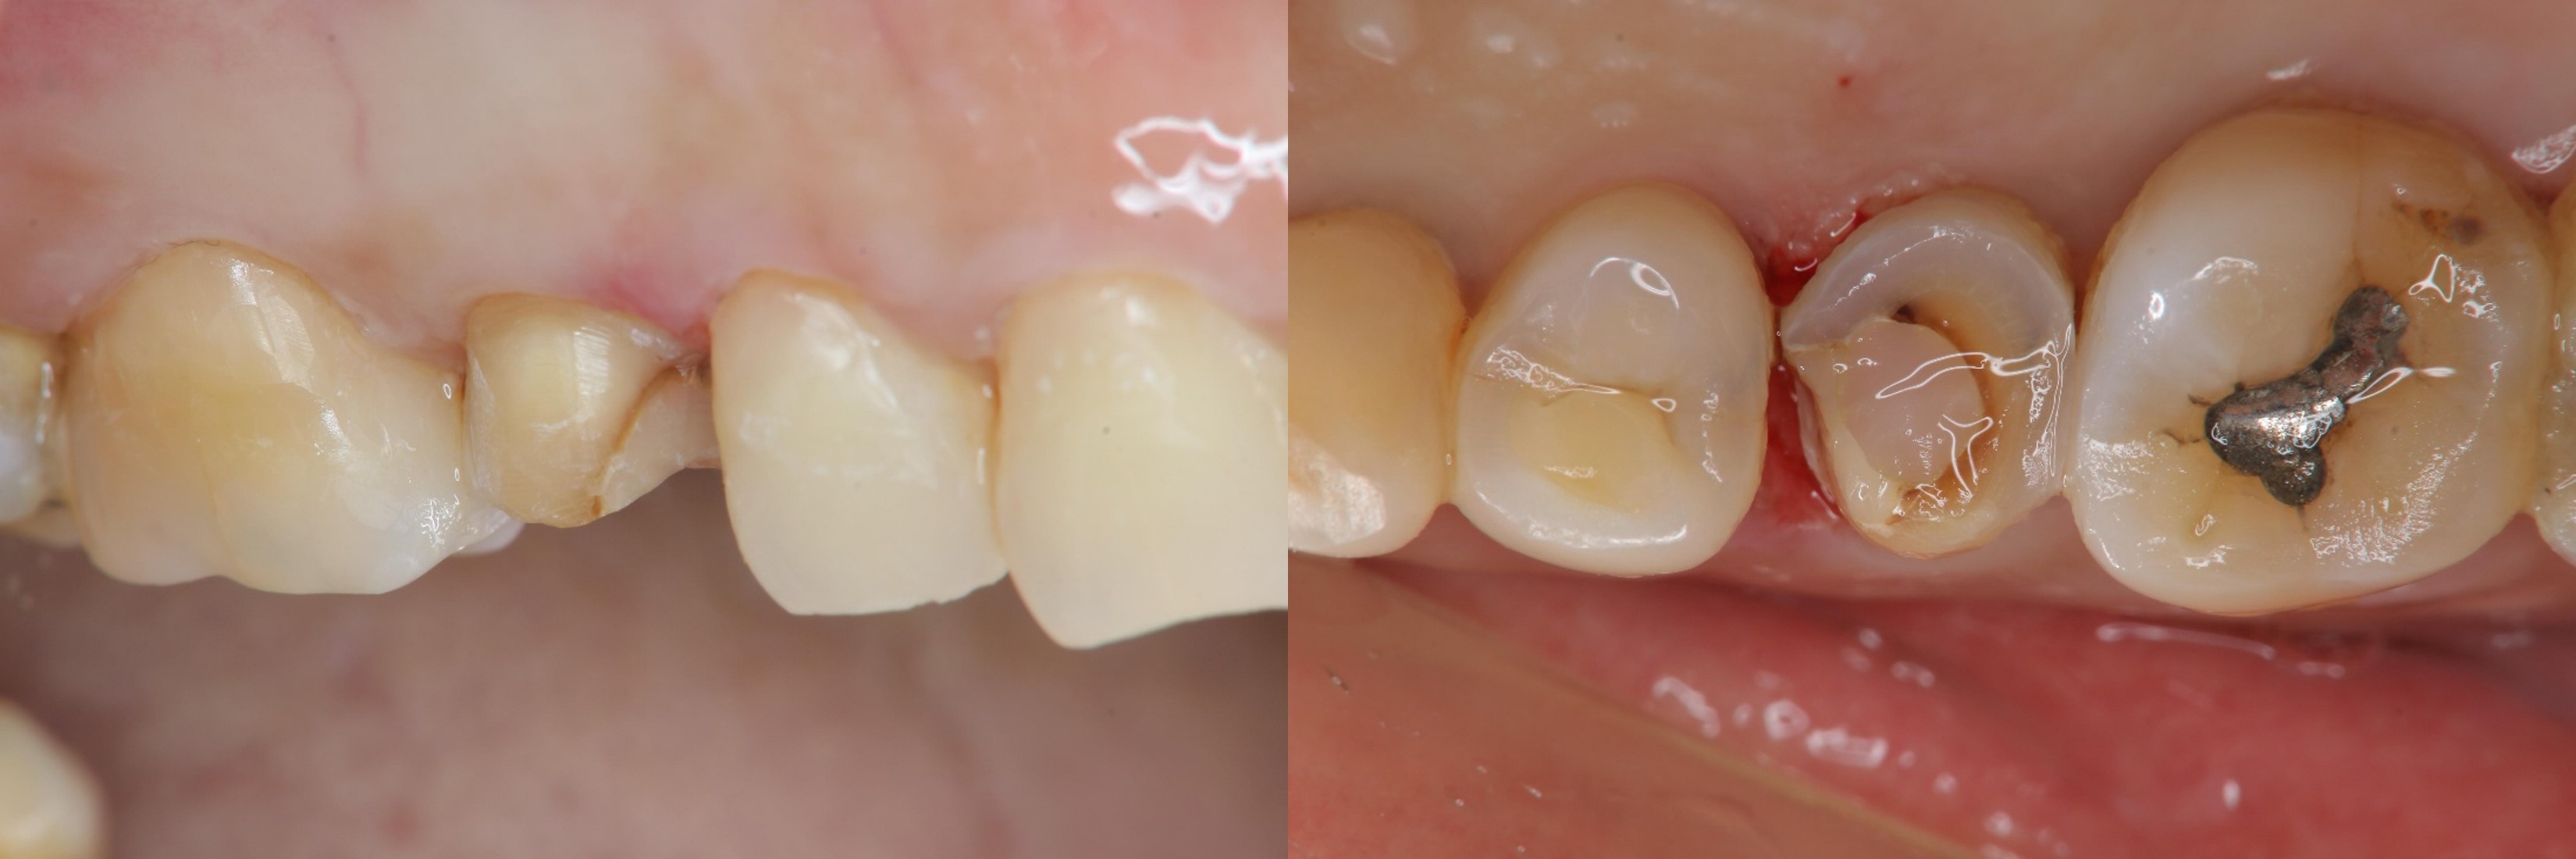

陶瓷冠塊體製備

陶瓷冠塊體口內黏著

治療後口內照

術前、術後比較